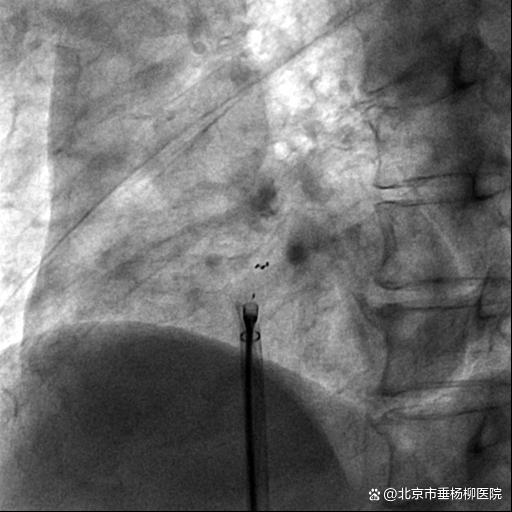

但是可降解封堵器无金属支架,可塑性和顺应性均较传统的金属封堵器要弱,增加了手术的难度,且封堵器在X线下不能完全显影,对于手术的引导手段提出了更苛刻的要求,目前多数医院采用经食管超声引导,这就需要全程麻醉,增加了手术风险和病人的痛苦,团队经过术前反复讨论,为其量身定制了目前更安全和可靠的四点标记的可降解封堵器应用X线及经胸心超的极简式引导手术方案。手术顺利进行,术中心房造影和术后心超均显示卵圆孔彻底闭合,无残余分流。术后第三天患者顺利出院。